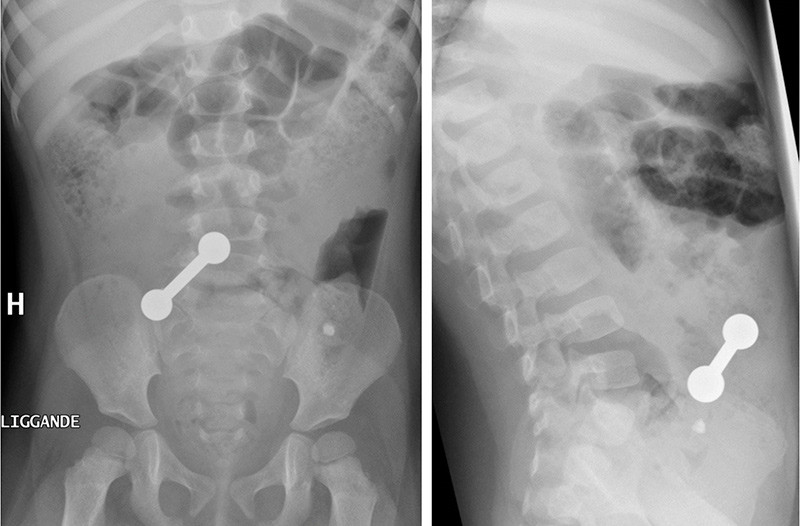

Det ble gjort ultralyd abdomen, som viste et fremmedlegeme i tarmen. Røntgen oversikt abdomen viste et 1,5 × 5,5 cm røntgentett fremmedlegeme formet som en pinne med en kule i hver ende. Foreldrene husket etter hvert at barnet fire måneder i forveien hadde spist tre magnetleker. De hadde regnet med at lekene ville passere.

Jenta ble laparotomert, og man fant intraoperativt to magneter i ileum som hang sammen over tarmveggen med en magnet i sigmoideum. Det hadde dannet seg en ileosigmoidal fistel. Magnetene ble fjernet og fistelen lukket. Det postoperative forløpet var ukomplisert.